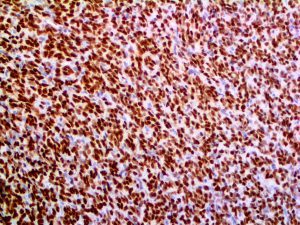

The first cytokines released are interleukin 1β (IL-1β) and tumor necrosis factor-α (TNF-α), which attract a variety of circulating white blood cells (WBCs) to the infection site, including neutrophils, monocytes, macrophages, and natural killer (NK) cells. This response, along with the antipathogenic chemicals released by these cells (i.e., complement), comprise the innate immune response. These cells directly attack the invading pathogen and also release additional cytokines, chief among them interleukin-1 and 6 (IL-6). IL-6 is essential for invoking the adaptive immune response, which calls T-cells, B-cells, and T helper (Th) cells to the infection site. IL-6 also stimulates further recruitment, proliferation and activation of macrophages.

It is the ICU physician who is most likely to witness one of the deadliest manifestations of the abnormal immunological response, the cytokine storm syndrome (CSS). This response is also referred to by some as the cytokine release syndrome (CRS). CSS is characterized by continuous activation and expansion of macrophage and lymphocyte populations, which secrete large amounts of cytokines, causing the cytokine storm. This massive cytokine release is akin to hemophagocytic lymphohistiocytosis (HLH) disease, a syndrome characterized by initial unchecked and persistent activation of cytotoxic T lymphocytes and NK cells.

Clinical and laboratory manifestations of HLH include fever, enlarged liver and/or spleen, neurologic dysfunction, coagulopathy, liver dysfunction, cytopenias (i.e., low levels of erythrocytes, leukocytes, and/or platelets), hypertriglyceridemia, hyperferritinemia, hemophagocytosis, and eventually diminished NK cell activity as the immune system becomes progressively paralyzed. HLH can be familial (primary HLH) or secondary to another disease process (sHLH), such as rheumatic disease, in which it is referred to as macrophage activation syndrome (MAS, characterized by elevated ferritin).

This activation induces inflammatory monocytes to highly express IL-6, starting a localized and then systemic cascade effect that results in hyperproduction of IL-6, which accelerates the inflammatory process. Because IL-6 also increases vascular permeability, excessive levels cause blood vessels to become very leaky. This, along with clotting factors released from vascular endothelial cells, stimulates the coagulation cascade, resulting in microthrombosis (tiny clots), which leads to ischemia and tissue death of the kidney, intestines, heart, liver, brain and extremities.